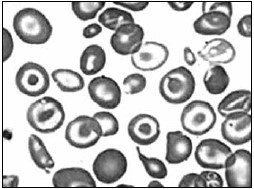

Paciente, masculino 39 anos, foi à Unidade de Pronto Atendimento no ABC Paulista, devido a equimoses nos membros inferiores e superiores. Relatou febre de 38 ºC por dois dias consecutivos e coceira intensa no corpo. O médico plantonista solicitou a realização de um hemograma. O laudo do hemograma demonstrou as seguintes concentrações de celularidades:

Foi realizado o esfregaço sanguíneo para confirmação do laudo. Assinale a alternativa que apresenta a descrição das células sinalizadas a seguir e a patologia a qual correspondem.

Figura 2

Enunciado 3519103-1

(Laudo e imagem cedidos pelo Laboratório de Análises Clínicas do Centro Universitário FMABC)